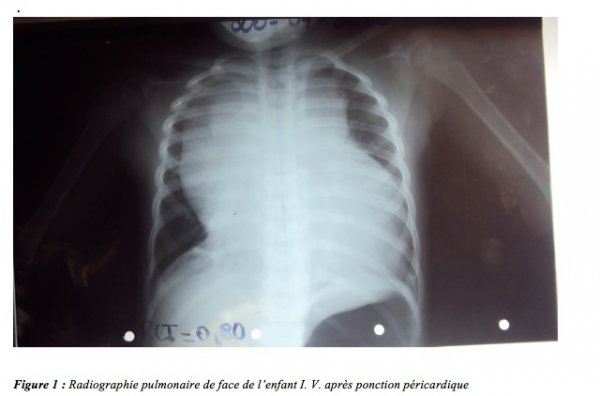

A l’admission, l’examen physique notait une détresse respiratoire avec une insuffisance cardiaque droite. L’auscultation cardiaque et pulmonaire était normale. Les explorations paracliniques ont révélé une anémie à 94 g/l, un taux normal de plaquettes à 198 000/ mm³, une hyperleucocytose à 137000 cellules/mm³ avec 27440 polynucléaires neutrophiles /mm³ et 104 272 lymphocytes/mm³, une cardiomégalie avec un index cardiothoracique de 0,8 associé à un élargissement du médiastin et un parenchyme pulmonaire normal (fig. 1). L’électrocardiogramme avait mis en évidence une tachycardie sinusale à 110cycles /min, des troubles de la répolarisation à type d’onde T négative en antéro-septoapical. L’échocardiographie avait montré un épanchement péricardique circonférentiel mesurant 16,8 mm en regard du ventricule droit ; une ponction péricardique réalisée en urgence a permis de soulager la patiente. L’étude tomodensitométrique du thorax avait mis en évidence une masse hétérogène du médiastin antérieur dont les caractéristiques faisaient suspecter un lymphome.

L’induction a été réalisée avec la Dexaméthaxone, la Vincristine et l’Aspanaginase pendant une période de 28 jours suivie des phases de consolidation et d’intensification. Le bilan de fin d’induction le 17.09.10 avait noté une rémission incomplète malgré une amélioration de l’état clinique. Au myélogramme on notait une moelle pauvre avec présence de mégaloblastes et 5% de lymphoblastes. La cytologie fine du LCS montrait une absence d’éléments cellulaires. La radiographie pulmonaire était normale de même que l’Hémogramme (leucocytes = 4700 /mm³ pour 3666 /PNN et 799/ mm³ Lymphocytes ; Hb = 119 g/l, plaquettes = 372000 /mm³).